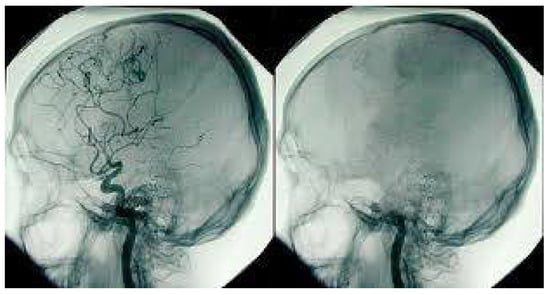

• This further exerts pressure on the brain, causing further brain injury. The doctors, at this stage, are working on the patient with various treatment methods. If these treatments fail, the brain may get so damaged that at some stage, all functions of the brain will be lost. Once a brain cell dies it is permanently lost; the body cannot regenerate brain cells. The high pressure inside the skull will stop all blood flow into the skull; this can be diagnosed by an angiogram (Figure 2) or a special brain scan (Figure 3).

Often clinicians can declare death after clinical testing. Sometimes, when clinical testing cannot be performed or clinicians are not satisfied during the process of testing (e.g., if the patient could not complete an Apnoea test), clinicians may request a radiological investigation to confirm the ‘absence of blood flow to the brain’, as mentioned previously—this process involves transporting the patient to the radiology department and undertaking an angiogram or a Technesium brain scan (neuroimaging). These investigations are then reported by appropriately trained radiologists, upon which the clinicians then decide whether to determine brain death.

Figure 2. Cerebral Angiogram showing normal blood supply on the left and no blood supply on the right. Photo Source: Australian Donor Awareness Programme and Training (ADAPT).